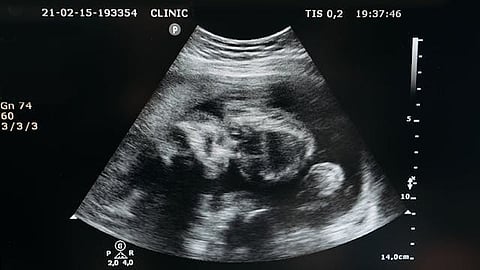

The science of AWT is real, although limited. Current experiments represent partial ectogenesis: where a foetus begins developing in the uterus and is then transferred to an artificial womb to continue its growth. Scientists in the US, the Netherlands and Japan have sustained premature animal foetuses in external ‘biobags‘.

Full ectogenesis (a baby never incubated in a human womb) may still be decades away, dependent on breakthroughs in placental bioengineering, infection control, and safely initiating embryo growth outside the uterus. But history suggests we should not underestimate incremental breakthroughs. In-Vitro Fertilisation (IVF) too, was once dismissed as fantasy until Louise Brown, the first ‘test-tube baby’, was born in 1978.